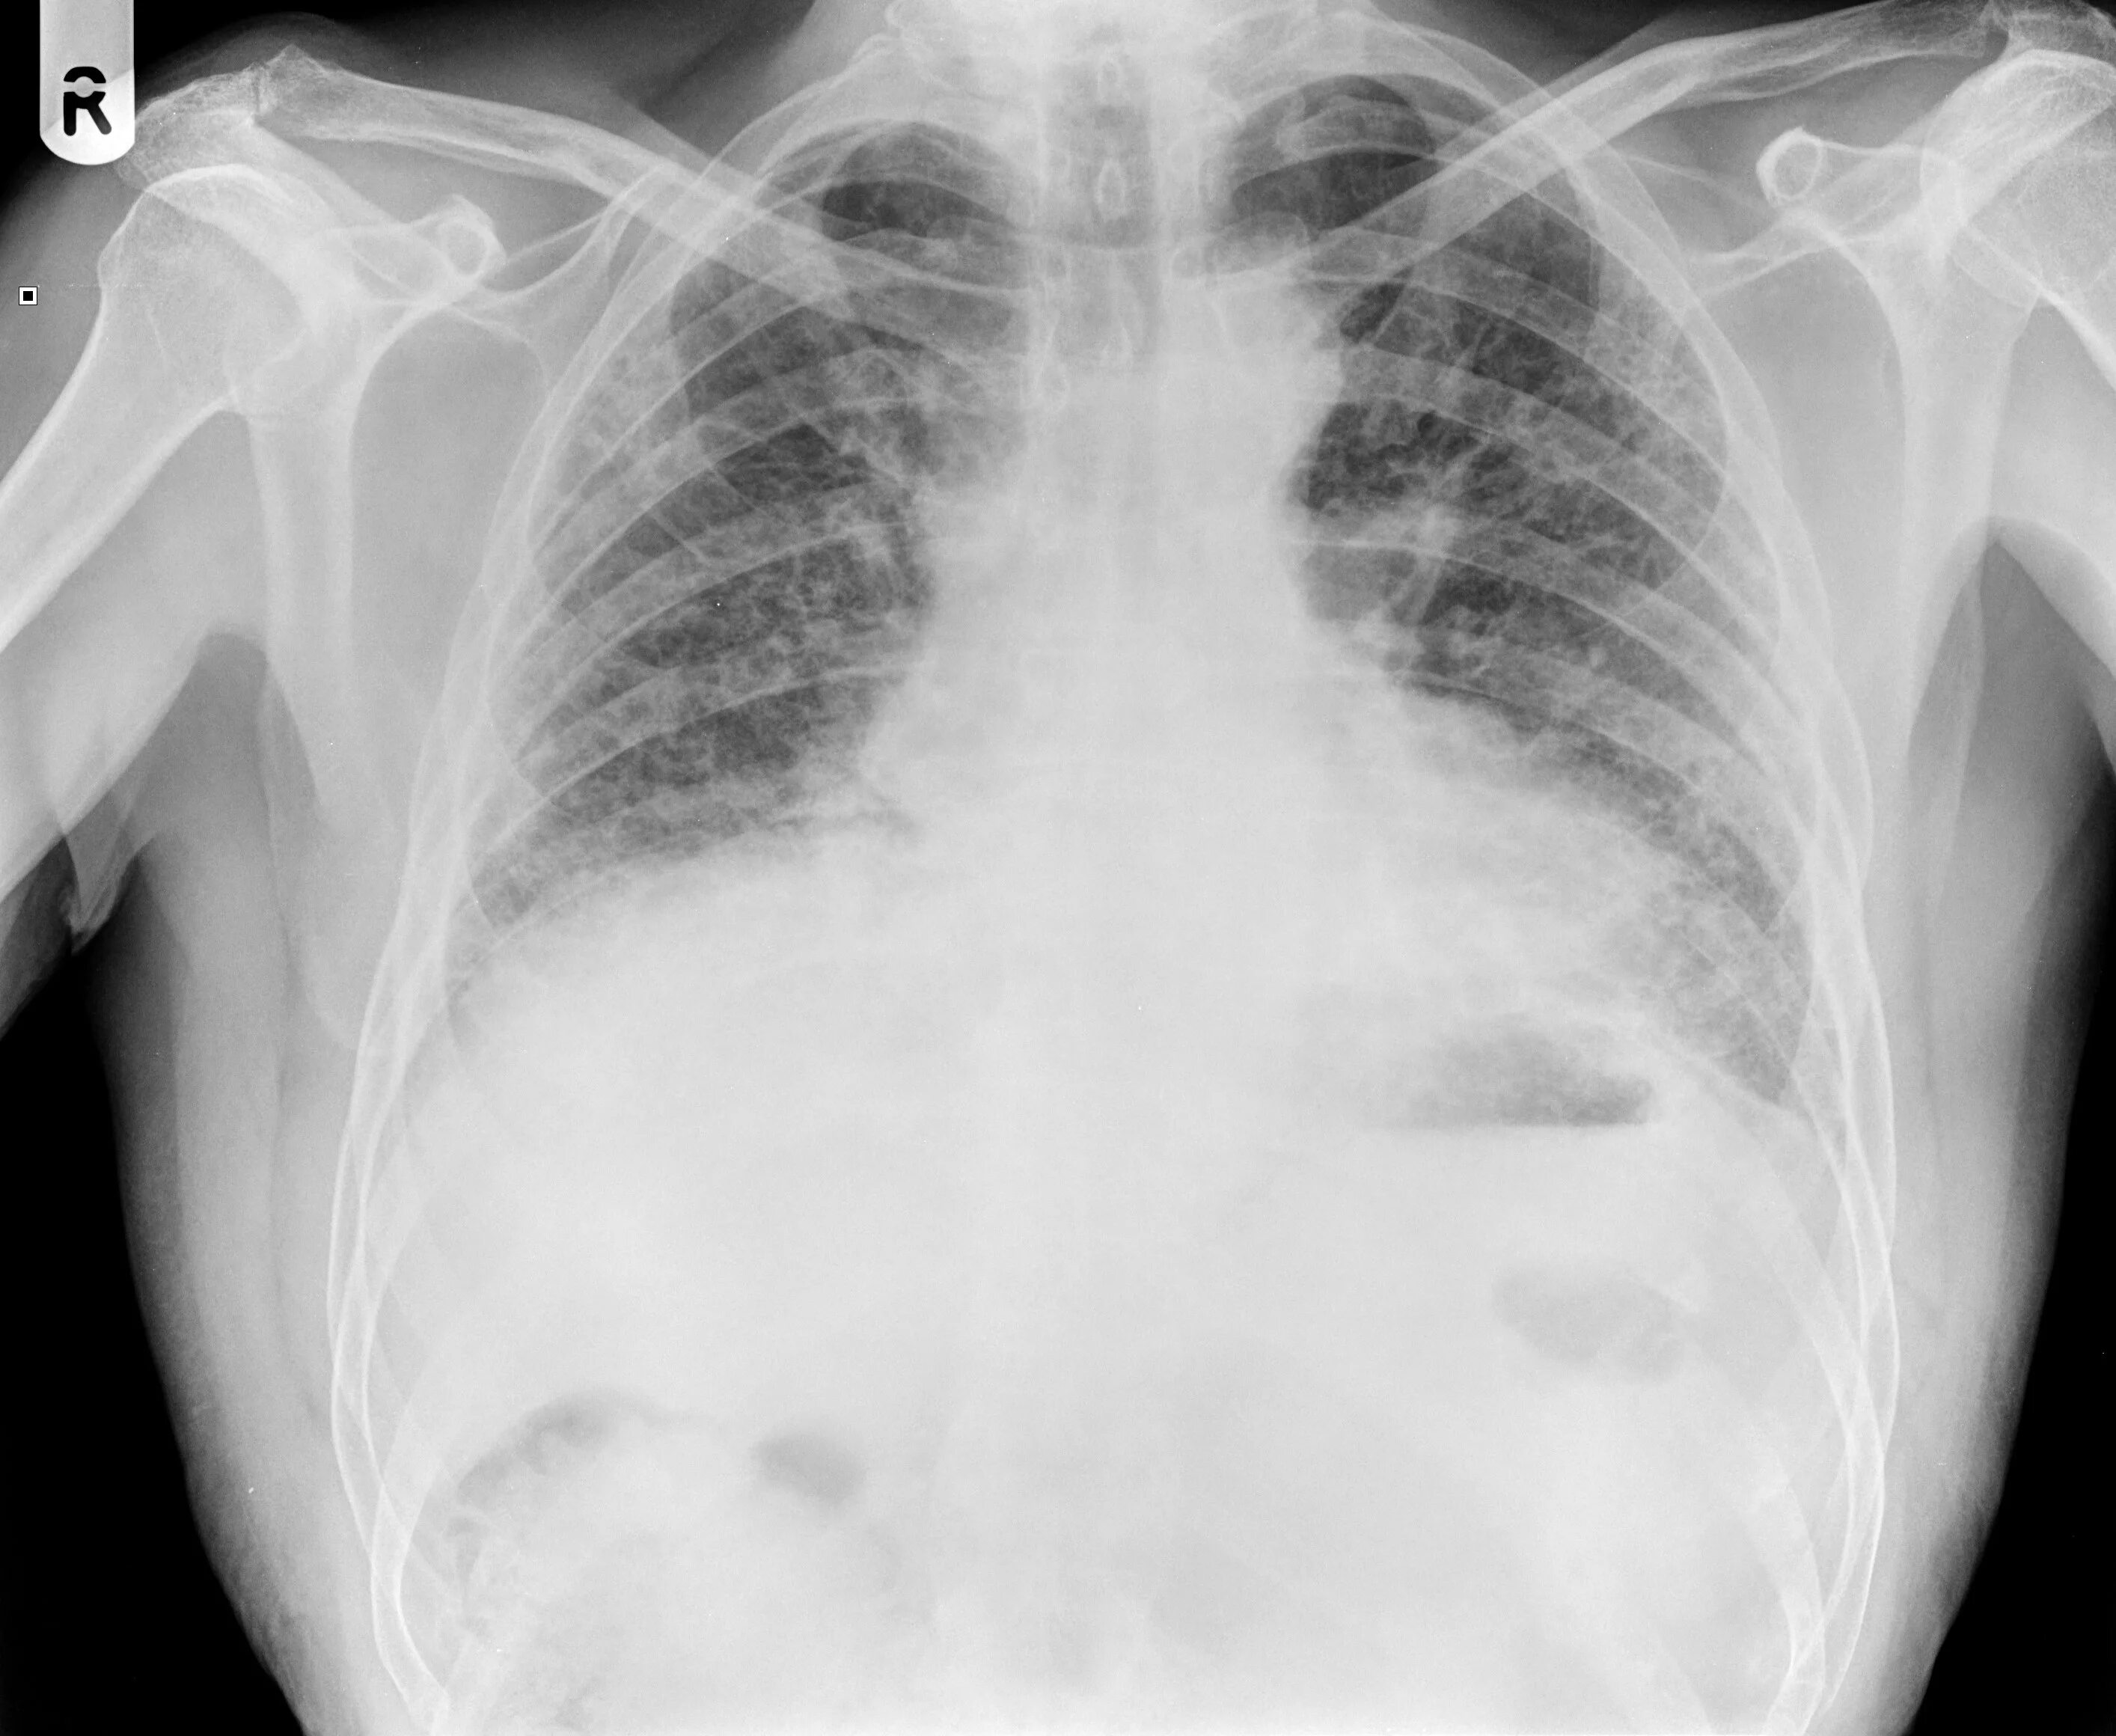

Диффузный пневмосклероз